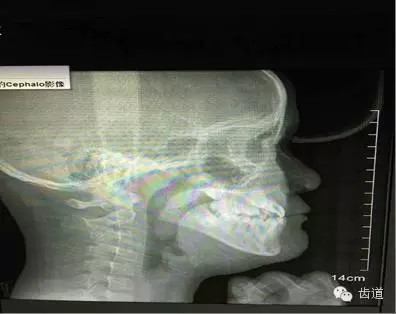

病例一:(權(quán)老師上傳的側(cè)位片圖1),在照片中,你會(huì)關(guān)注哪些情況呢?

圖1

權(quán)老師從(牙合)學(xué)的角度提出:

以上側(cè)片中應(yīng)關(guān)注舌的位置,由此會(huì)引發(fā)出更多需要關(guān)注的問(wèn)題(如:舌的位置是否與氣道、牙弓狹窄、中線偏斜等有關(guān))。